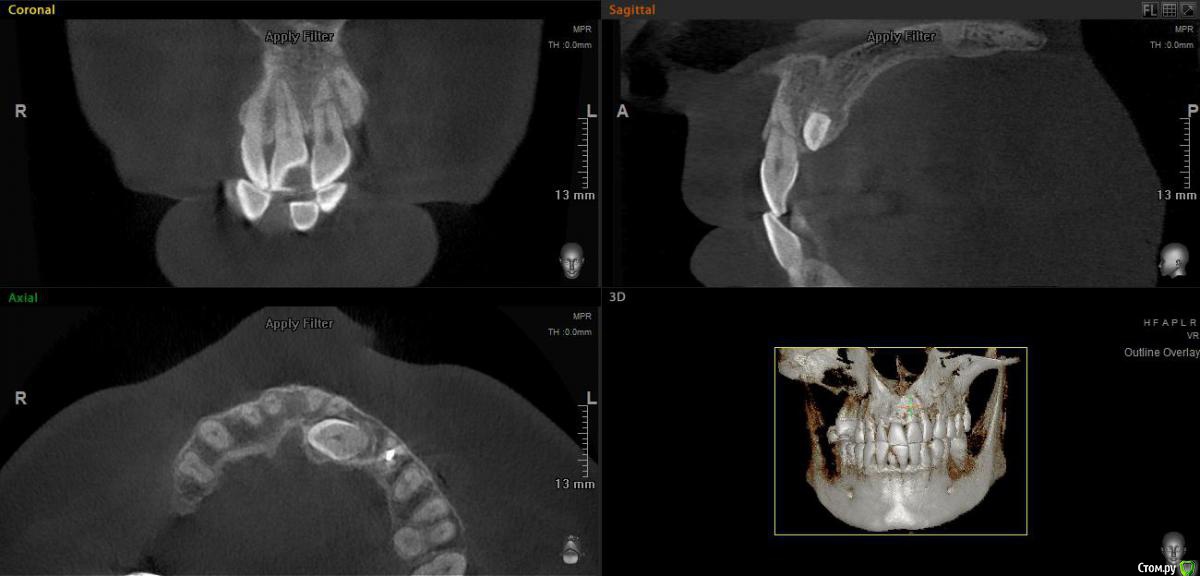

elen_only Опубликовано 10 февраля, 2020 Поделиться Опубликовано 10 февраля, 2020 Доброго дня всем,коллеги! Всех с прошедшим Днём стоматолога! Открыла тему в терапии и здесь продублирую. Ситуация такая:направил ко мне ортодонт на резекцию верхушки корня молодого мужчину. В анамнезе травма передних зубов,лет 10 назад. Год назад поставили брекет-систему. Иногда жалуется на небольшую болезненность при накусывании. Зуб подвижен,в цвете не изменён. Прикрепляю снимки,разница между первым и вторым-год. Доктор не заметила перелом корня зуба 21 и поставила брекеты. Удалить зуб и вкрутить сразу имплантат (как хотелось бы) не получится,у пациента ретинированный клык,который будут пытаться вытянуть. В связи с этим вопрос: как сохранить этот зуб,хотя бы до момента ,когда вытянут клык? Думала запломбировать верхнюю часть и удалить верхушку,но в общем-то за год никаких периапикальных изменений не появилось,кроме резорбции отломков,может и не трогать. Как правильнее поступить?1.запломбировать верхнюю часть,не трогать верхушку2. Запломбировать верхнюю часть и удалить верхушку3. Вообще не трогать зуб,сколько постоит.И если пломбировать,то чем? И как мыть эту часть гипохлоритом,чтобы не вышел куда не надо? Вдруг,кто сталкивался с таким Ссылка на комментарий

Astronaft Опубликовано 12 февраля, 2020 Поделиться Опубликовано 12 февраля, 2020 (изменено) http://miworks.weebly.com/uploads/1/6/8/7/16879370/9508255_orig.jpg http://miworks.weebly.com/uploads/1/6/8/7/16879370/2163396_orig.jpg У меня есть такой пациент. Зуб витальный, наблюдал около 3 лет. Сначала зашинировал, потом все снял. Все в порядке, кроме повышенной подвижности.Не спешите списывать зуб. У природы огромные силы к восстановлению. Изменено 12 февраля, 2020 пользователем Astronaft Ссылка на комментарий